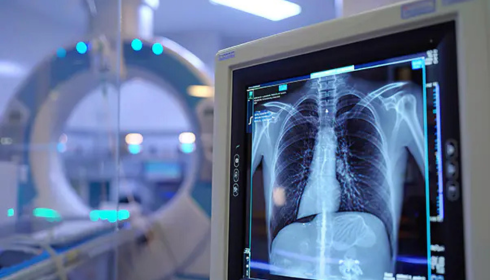

Radiology Solutions refer to imaging technologies used to capture and analyze medical images. They include X-rays, CT scans, and tools that help doctors detect diseases early. These solutions focus on speed, precision, and patient safety. They reduce errors and improve workflow efficiency. Better imaging allows professionals to create accurate diagnoses and effective treatment plans without delays.

The DR400i is a flexible digital radiography system designed for performance and ease of use. It supports multiple applications and delivers high-quality images quickly. The system suits hospitals and diagnostic centers needing reliable imaging solutions. DR400i improves patient comfort with a user-friendly design and smooth operation. It also supports efficient workflow, helping teams manage more cases without losing accuracy.

AGFA is a trusted name in medical imaging and delivers advanced Radiology Solutions for modern healthcare needs. AGFA focuses on innovation, quality, and reliability, ensuring consistent performance. With AGFA Digital systems, providers can improve workflow and manage data efficiently. The DR400i by AGFA offers flexibility, speed, and accurate results across clinical settings. AGFA also provides strong support and training for effective system use. Choosing AGFA means investing in proven technology that improves diagnostic confidence and patient care every day.